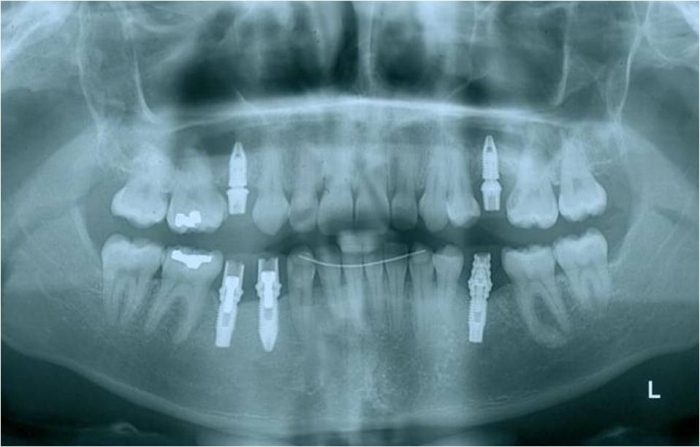

Raio x final